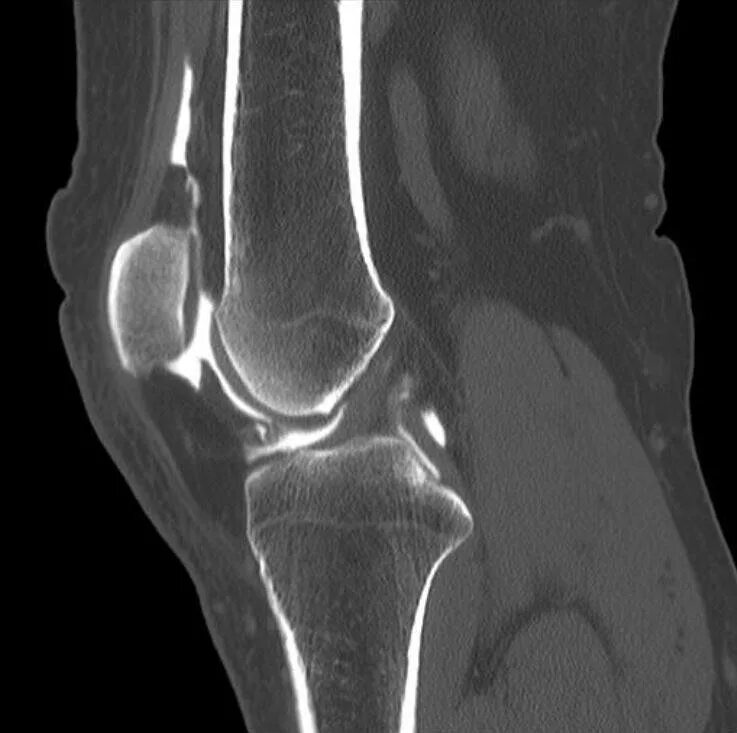

Кт суставов что показывает